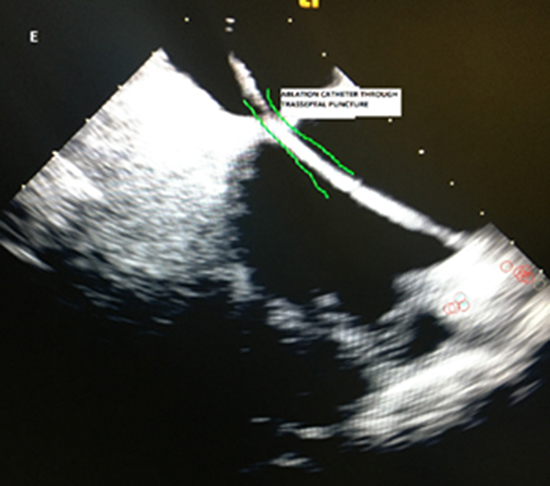

Figure 2. ICE image showing the bidirectional Ablation Catheter through the transseptal puncture.

Taking into consideration that our patient was in therapeutic INR (for transhepatic approach the INR is vital to be within normal range) and, furthermore, that the patient’s family required the procedure to be done as scheduled, it was decided to move forward with right subclavian access through which a deflectable catheter was advanced and positioned in the coronary sinus (CS) for left atrial (LA) pacing and recording purposes. Left subclavian venous access was found to be appropriate after peripheral venography. Left axillary vein was cannulated and a 10-French sheath and an Agilis sheath were advanced and positioned. Intra-cardiac Echo (ICE) catheter was advanced and positioned. Intravenous heparin bolus (100U/kg) was given to maintain active clotting time (ACT) between 250-300. ICE images were reversed (superior to inferior) in order to visualize the septum as coming from the IVC. We advanced a Baylis needle into the Agilis sheath. As we would advance the needle, the sheath would fall off the septum despite curve changes. Since extreme difficulty was faced to maintain the needle at the septum, we decided to use the Baylis wire instead of the needle. The Baylis wire was placed the septum and the transseptal puncture was performed. The puncture site was relatively superior on the septum. A 0.035mm caliber wire was advanced through the transseptal puncture site. It was difficult to get the dilator and the Agilis sheath across the septum so we exchanged the Agilus with the SL1, which was unfruitful too. The SL1 was replaced with a Vizigo sheath.